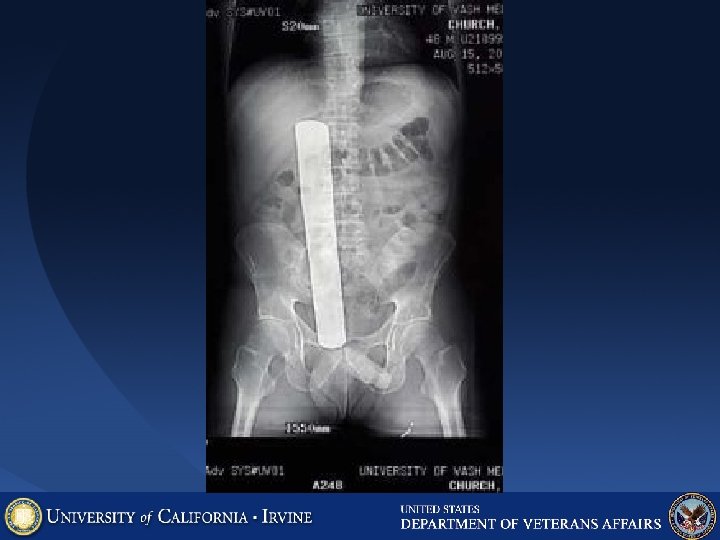

Post cath groin pain, tenderness, swelling, hematoma, bruit, low Hgb. What is this? Femoral Artery Pseudoaneurysm after cath